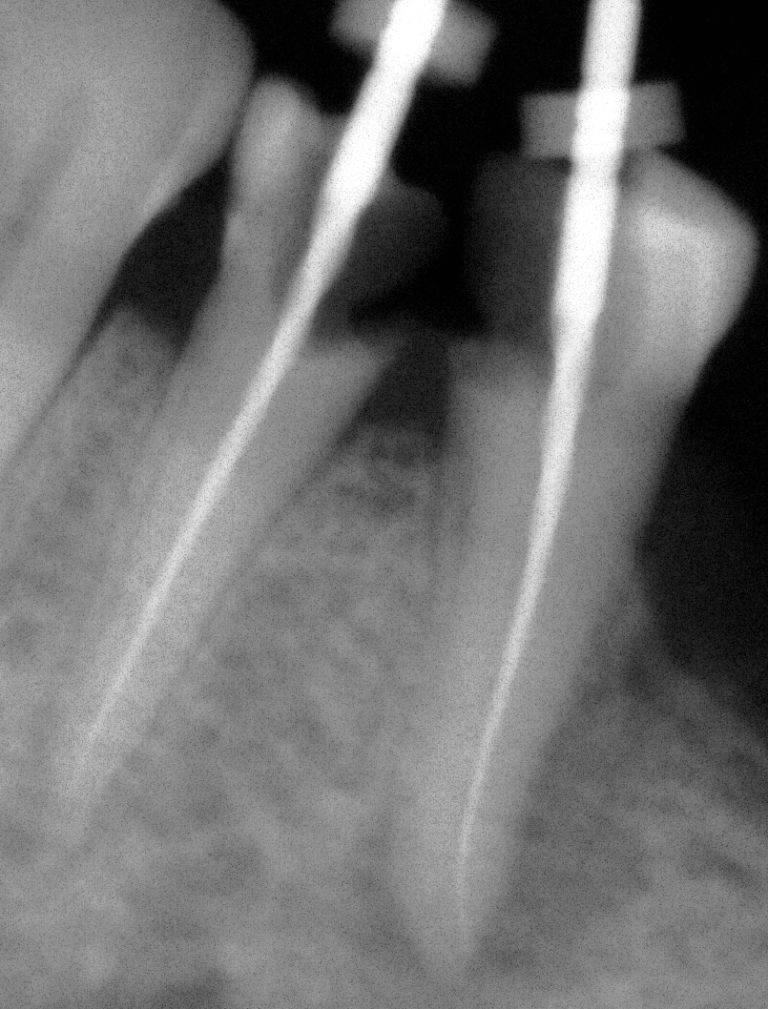

ROOT CANAL CASE OF PREMOLAR TEETH